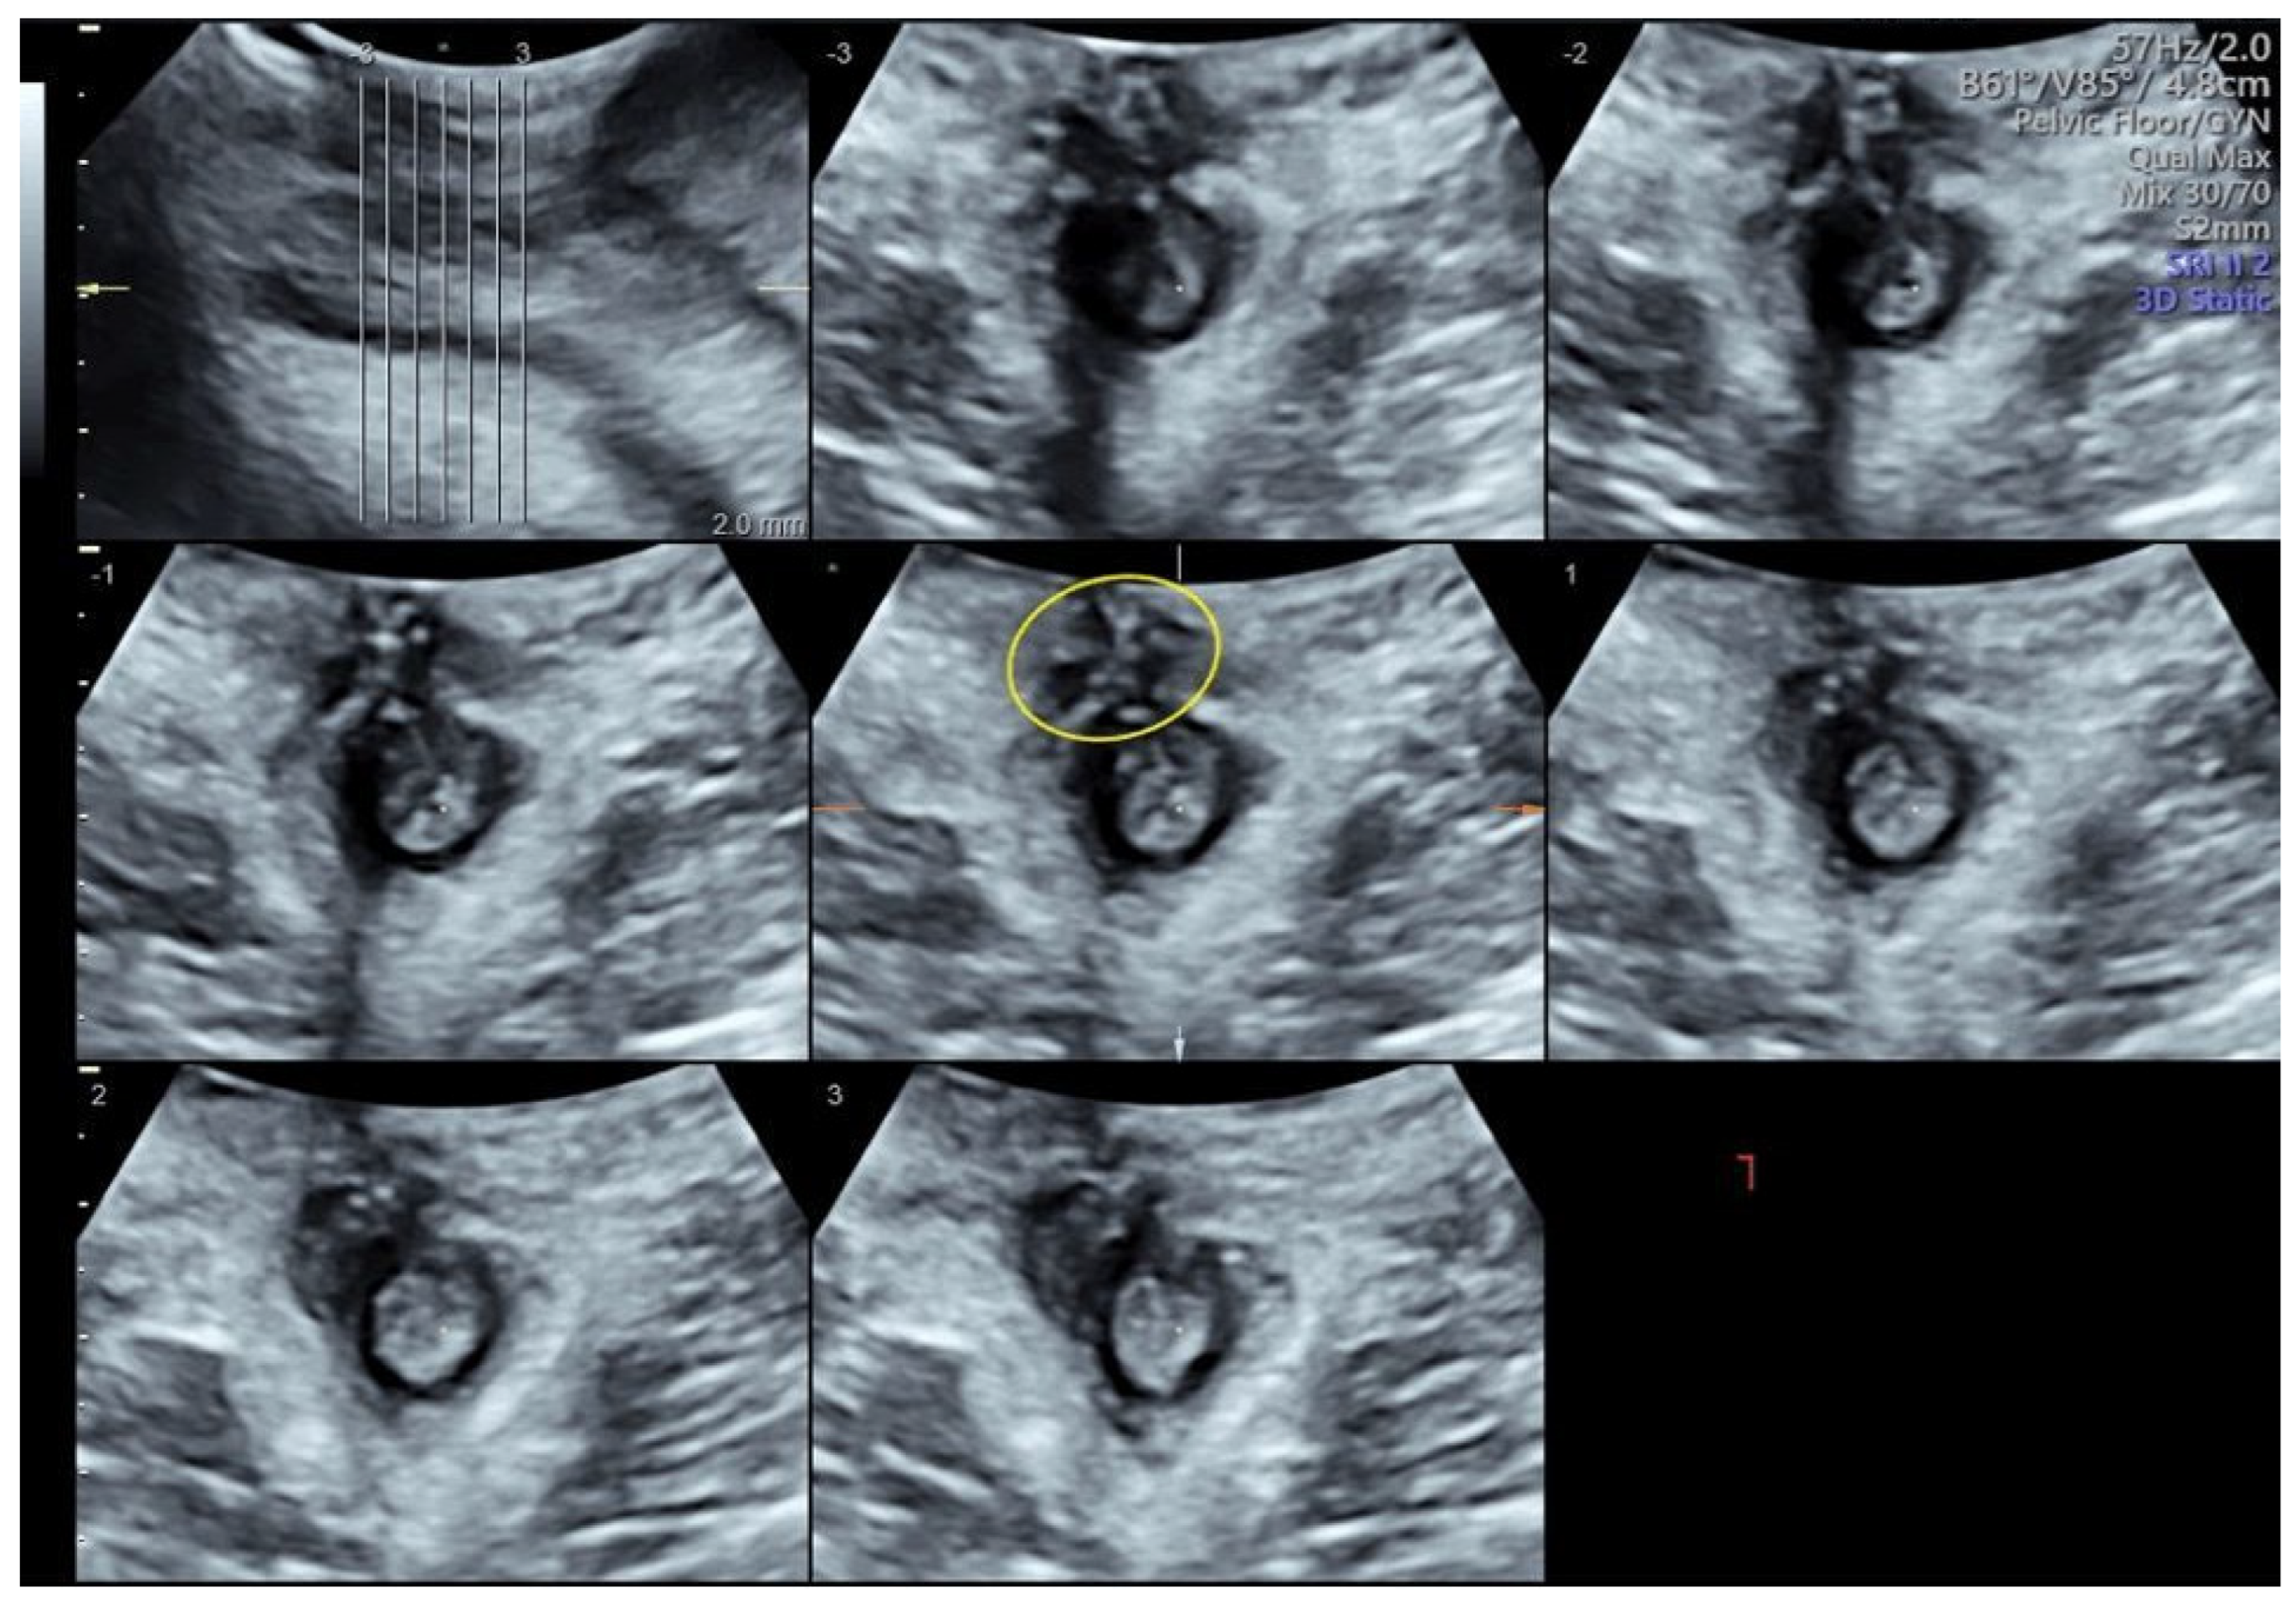

Three-Dimensional Transperineal Ultrasound Guiding Early Secondary Repair of Obstetric Anal Sphincter Injury in an Incontinent Patient without Suture Dehiscence

Orsi, M.; Cappuccio, G.; Kurihara, H.; Rossi, G.; Perugino, G.; Ferrazzi, E.; Coppola, C. Three-Dimensional Transperineal Ultrasound Guiding Early Secondary Repair of Obstetric Anal Sphincter Injury in an Incontinent Patient without Suture Dehiscence. Diagnostics 2024, 14, 68. https://doi.org/10.3390/diagnostics14010068